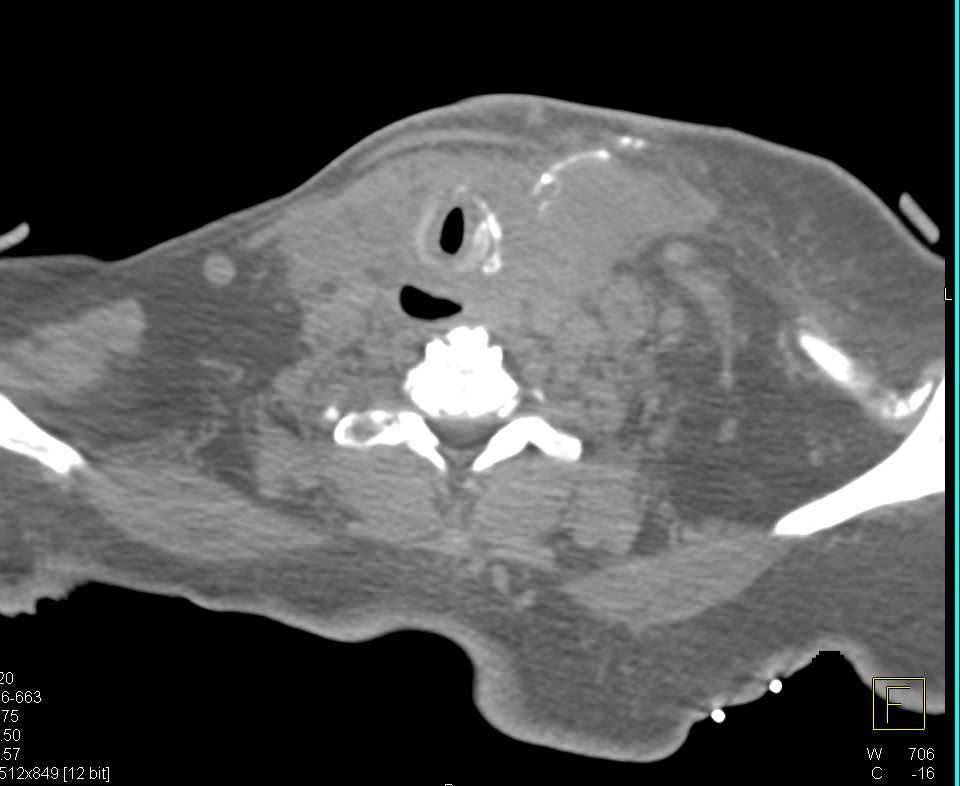

Esophageal Duplication Cyst